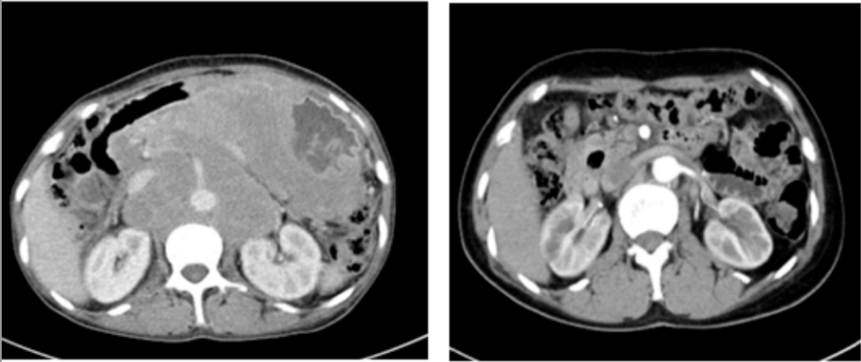

兩年前,張阿姨(化名)的生活被一場(chǎng)突如其來(lái)的疾病打亂。持續(xù)地惡心、嘔吐,整整一個(gè)月幾乎未進(jìn)食。在家人的陪伴下,來(lái)到國(guó)文醫(yī)院進(jìn)行全面檢查。胃鏡結(jié)果和腹部CT帶來(lái)了一個(gè)沉重的消息:胃部彌漫大B細(xì)胞淋巴瘤,并且已形成一個(gè)直徑約10厘米的巨大包塊。這不僅僅是一個(gè)腫瘤,更是一枚“不定時(shí)炸彈”。因?yàn)榱馨土龅那址?,張阿姨的胃壁已?jīng)形成了巨大潰瘍,隨時(shí)可能引發(fā)消化道大出血或穿孔,性命危在旦夕。

精密的策略迎來(lái)了勝利的曙光,四周期治療后復(fù)查胃鏡,原有的巨大潰瘍已完全消失。腫瘤得到有效控制,穿孔風(fēng)險(xiǎn)解除!在此基礎(chǔ)上,后續(xù)的四個(gè)周期治療調(diào)整為標(biāo)準(zhǔn)的R-CHOP方案,乘勝追擊,力求徹底清除病灶。

歷經(jīng)八個(gè)周期的規(guī)范化療,最終的評(píng)估結(jié)果讓所有人歡欣鼓舞:張阿姨的病情在影像學(xué)檢查上顯示腫瘤已消失。